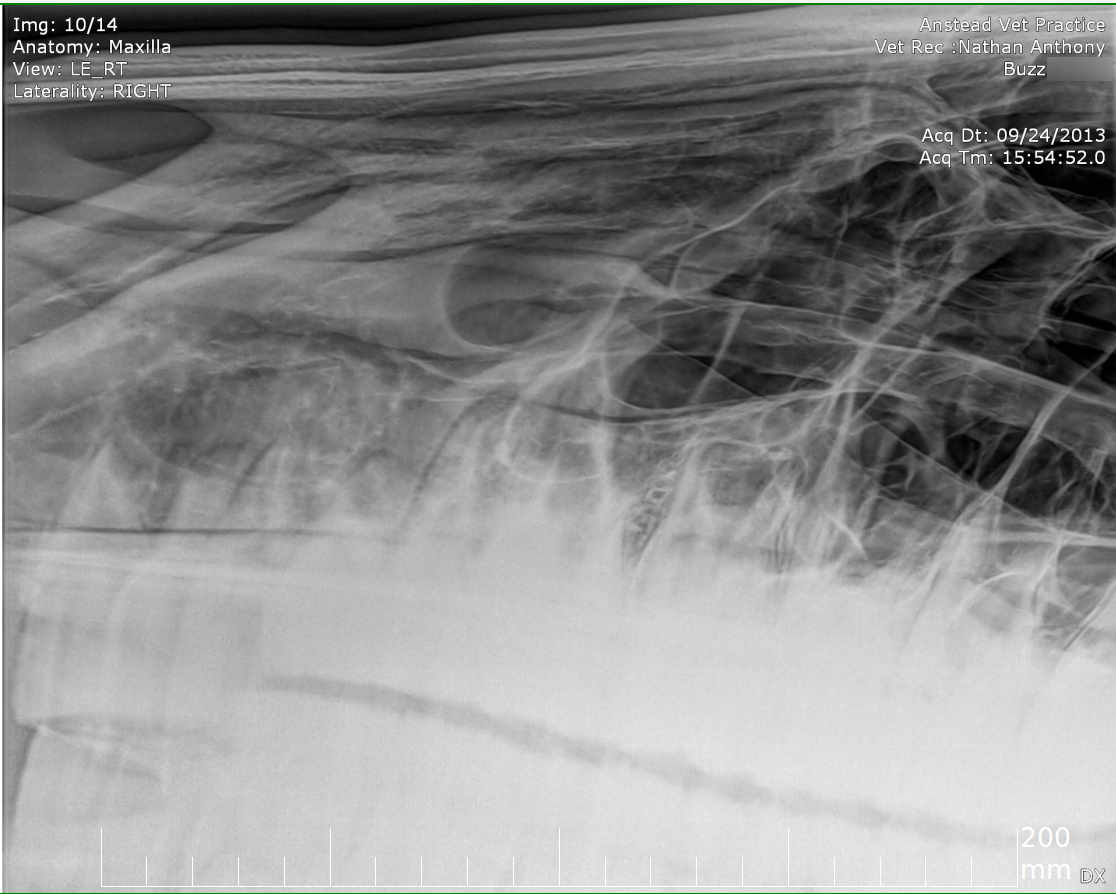

Posted on Sunday, May 8, 2016 - 6:24 pm: Thank you for the welcome!I did contact the lab to see if they still had the samples but they will only speak to the vets who submitted the samples. I've asked my vet to ask on my behalf but haven't yet heard back yet. The horse has been scoped and I was told that it all looked normal. The stylohoid bone and guttural pouches normal. The inflammation is mostly around the nostrils as per the pic but there are a couple of small spots further up inside the nose. He's also had his skull xrayed which I'm told also looked normal. I've included the pics at the bottom. I've included a list of other things here that have been tested to see if they influence the shaking or inflammation for the better or worse: - experimental course of Equity - Flixotide via inhaler - high dose of prednisolone - did work! - low dose of prednisolone - did not work - teeth checked by two different vet dentists - fly masks & nose nets - relocated him to several different places in the city incase it's an environmental allergen - all sorts of feed supplements - removed all hard feed, just feeding hay - stabled him 24/7 and fed him Haygain steamed hay incase it was something in the paddock - light/dark makes no difference to the shaking - it's not seasonal, happens year round I've also had bloodwork done and it showed a low red blood cell count. The blood was taken two weeks after the biopsies. My vet didn't think the low count was attributed to the blood loss from the biopsies so he suggested parasites but a worm count came back clean. I also had a test to see if there was blood in the manure, but nothing was found. There was no plan made to address the low RBC. Results are attached in a text file to maintain the spacing.

Xray images: